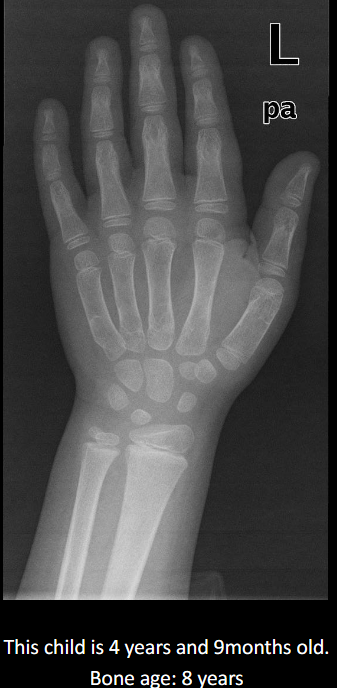

Define advanced bone age.

2 years ahead of chronological age.

List causes of advanced bone age.

Increase sex steroids, precocious puberty, endocrine disorders, CAH, familial tall stature, obesity.

Typical stature in advanced bone age.

Tall for age.

Standard imaging and method for bone age.

PA hand & wrist, Greulich & Pyle comparison.